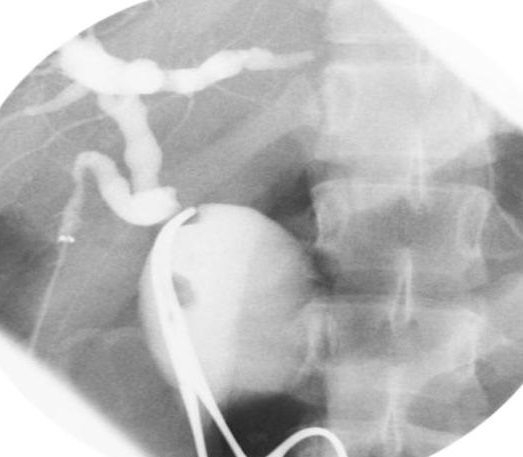

Cholangiographie percutanee

d'une atresie de voie biliaire de type 3 .On

a place une sonde dans la vesicule biliaire sous

echographie , la vesicule est normale , canal

cystique , canal choledoque sont permeable .Aucune

opacification du canal heapatique et des voies

biliaires intrahepatique est visible . |